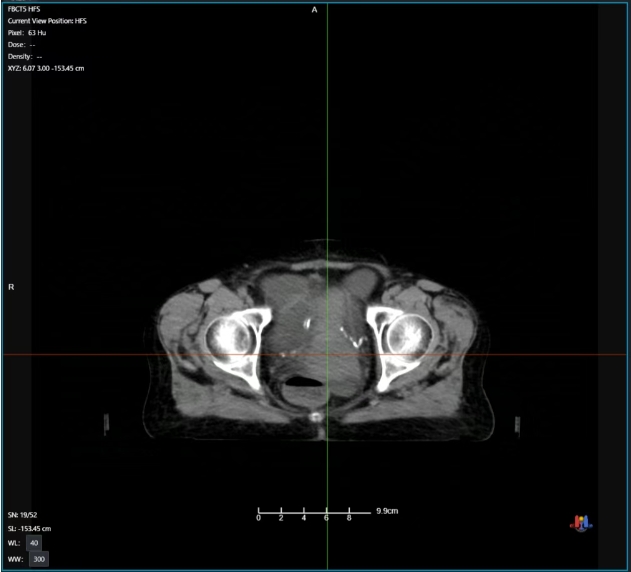

放疗后期病灶影像

整个放疗治疗周期中刘阿姨反馈为基本无无明显不适。通过治疗期间CT影像可发现,随着放疗次数增加病灶逐步减小,效果明显,最终该病灶基本消失!